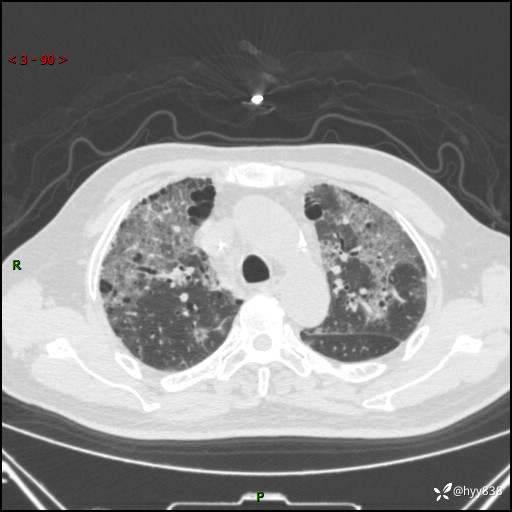

患者性别:男

患者年龄:64岁

简要病史:肝内胆管癌综合治疗后2周余,咳嗽、发热,咳白色泡沫痰。

辅助检查:CT

临床诊断:感染?

讨论:病变性质?